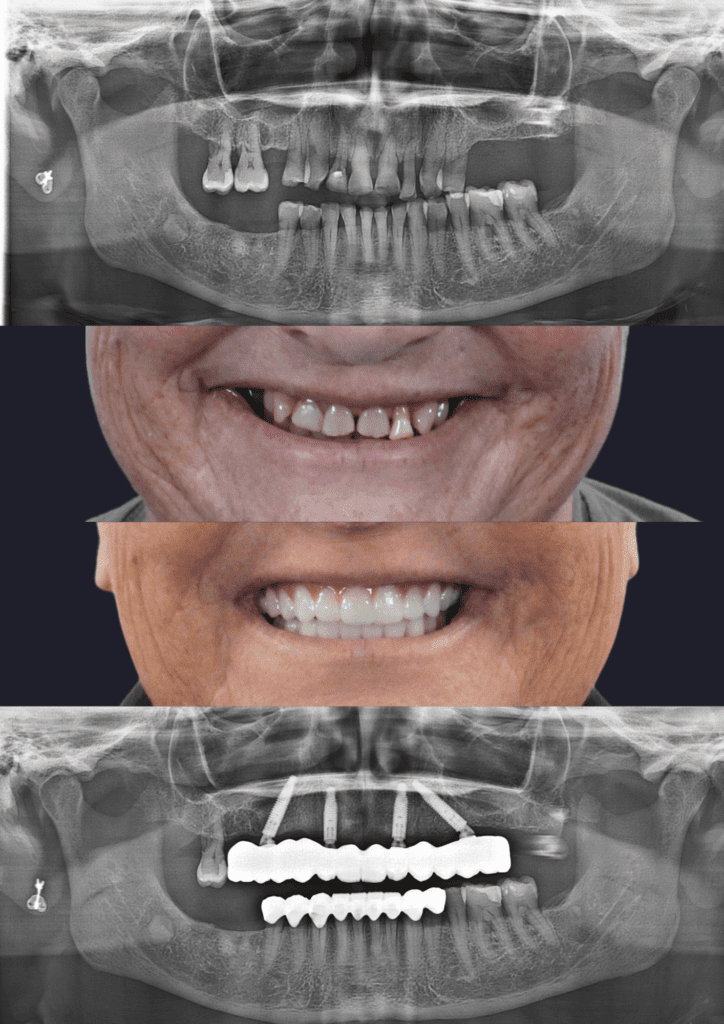

Before & After Treatment Gallery

The photos shown here document completed full-jaw implant treatments. Each case involved detailed planning, surgical placement of implants, and a custom-made fixed bridge. Treatment outcomes, timelines, and suitability vary and are assessed on a case-by-case basis.